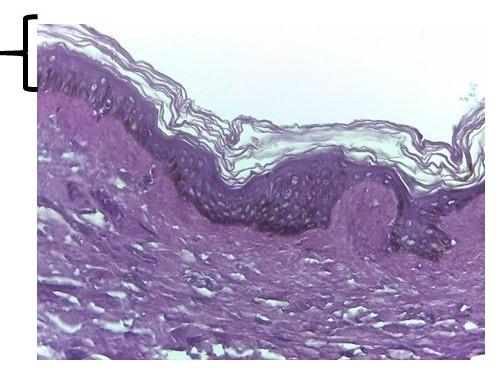

Identify the specific layer of the epidermis labeled 8

stratum corneum

Identify the specific layer of the epidermis labeled 9

stratum granulosum

Identify the specific layer of the epidermis labeled 10

stratum spinosum

Identify the specific layer of the epidermis labeled 11

stratum Basale

Identify the specific layer of the epidermis labeled 8

stratum corneum

Identify the specific layer of the epidermis labeled 9

stratum granulosum

Identify the specific layer of the epidermis labeled 10

stratum spinosum

Identify the specific layer of the epidermis labeled 11

stratum Basale